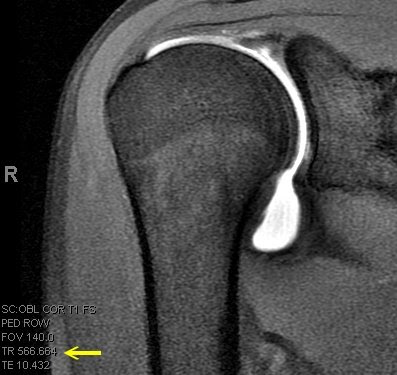

An MRI arthrogram exam is an imaging study. It is used to take detailed pictures of your joints. MRI stands for magnetic resonance imaging. This exam has 2 parts. First you will have an arthrogram and then an MRI. This 2-part exam shows more details of your joint than an MRI by itself. It will help your healthcare provider decide which treatment is best for your medical condition.

- Joints such as knee, hip, and shoulder are made up of 2 bones that fit closely together. Other tissues (cartilage, tendons, and ligaments) support and cushion your joints. An MRI arthrogram helps your doctor see small tears or other problems in these tissues. The results of this exam will help guide your treatment. It will also help your doctor keep track of problems in your joint.

Part 2: The MRI

- You will lie on a sliding table. The MRI technologist will help you get into position for the exam.

- A device called a surface coil will be placed around the joint that is being examined.